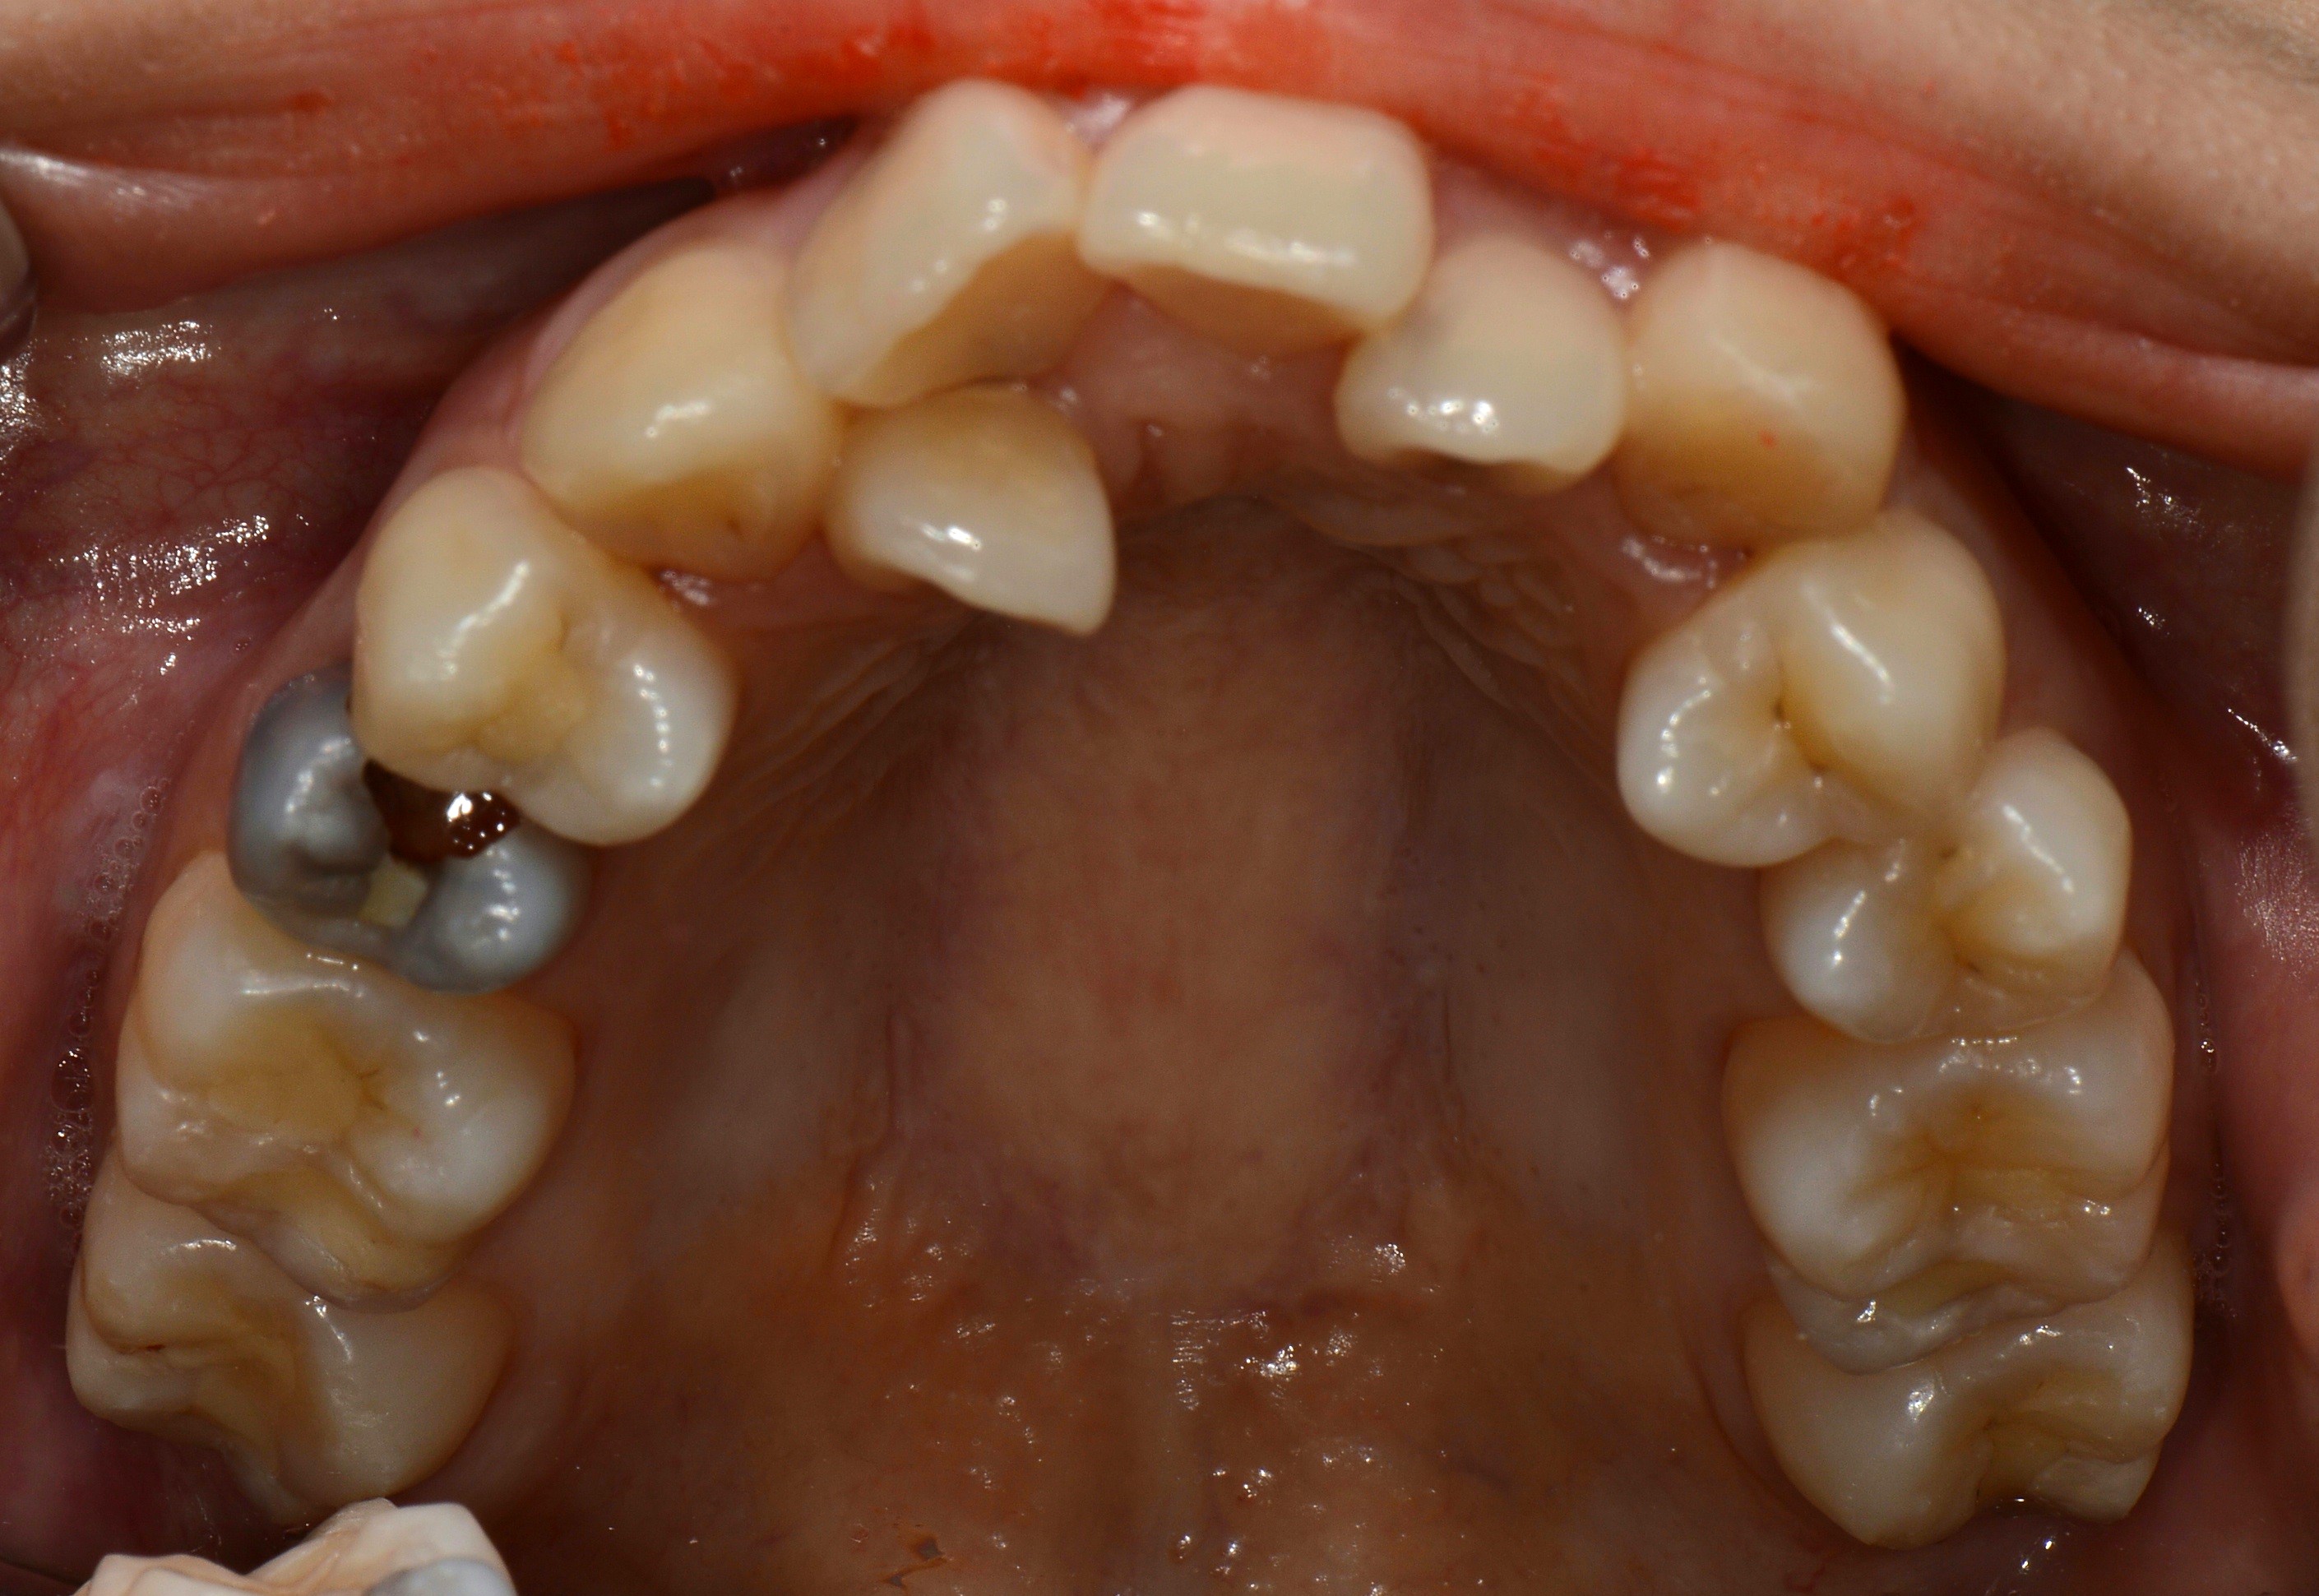

치료 전 사진입니다.